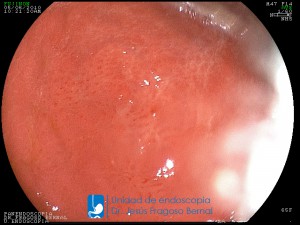

La Unidad de Endoscopía fue creada en 2002 por el Dr. Jesús Fragoso Bernal, es pionera en el estado por la utilización de la tecnología más avanzada, que nos permite ofrecer servicios integrales de diagnóstico y tratamiento para las enfermedades del aparato digestivo.

"La Unidad de Endoscopía se ha caracterizado por un progreso continuo desde su inicio marcando la pauta en los procedimientos endoscópicos en el estado de Tlaxcala y estando siempre a la vanguardia tecnológica."

Dr. Jesús Fragoso Bernal